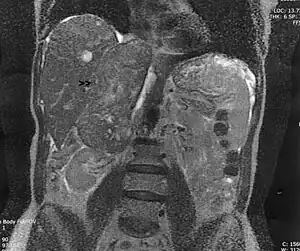

Surgem como uma massa que cresce, indolor, eventualmente palpável e visível em um exame de imagem, que pode causar náusea, vômito e perda de peso. Geralmente tem mais de 7cm no momento do diagnóstico.

Histologicamente pode-se diferenciá-lo de um leiomioma (benigno) por tamanho (mais de 8cm), muita celularidade, frequentes atipias, necrose, hemorragia e número de mitoses por campo de alta potencia. Um exame imuno-histoquímico pode detectar os marcadores específicos de músculo como desmina, antígeno muscular específico (HHF35), citoqueratina ou antígeno epitelial de membrana (EMA).[2]